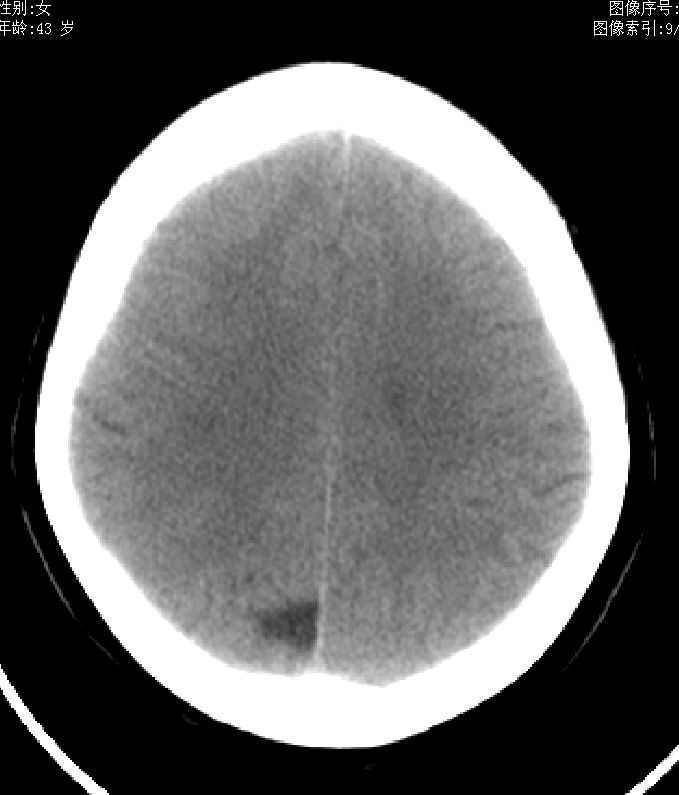

43岁,女性,头晕、语言含糊1天伴左侧肢体麻木,有高血压病史,bp160/100hg,余(-)。

脑沟或软化灶

脑沟或软化灶,建议增强或mr,最好mr

考虑右侧顶叶脑软化灶。

考虑右侧半卵圆中心陈旧性梗塞.